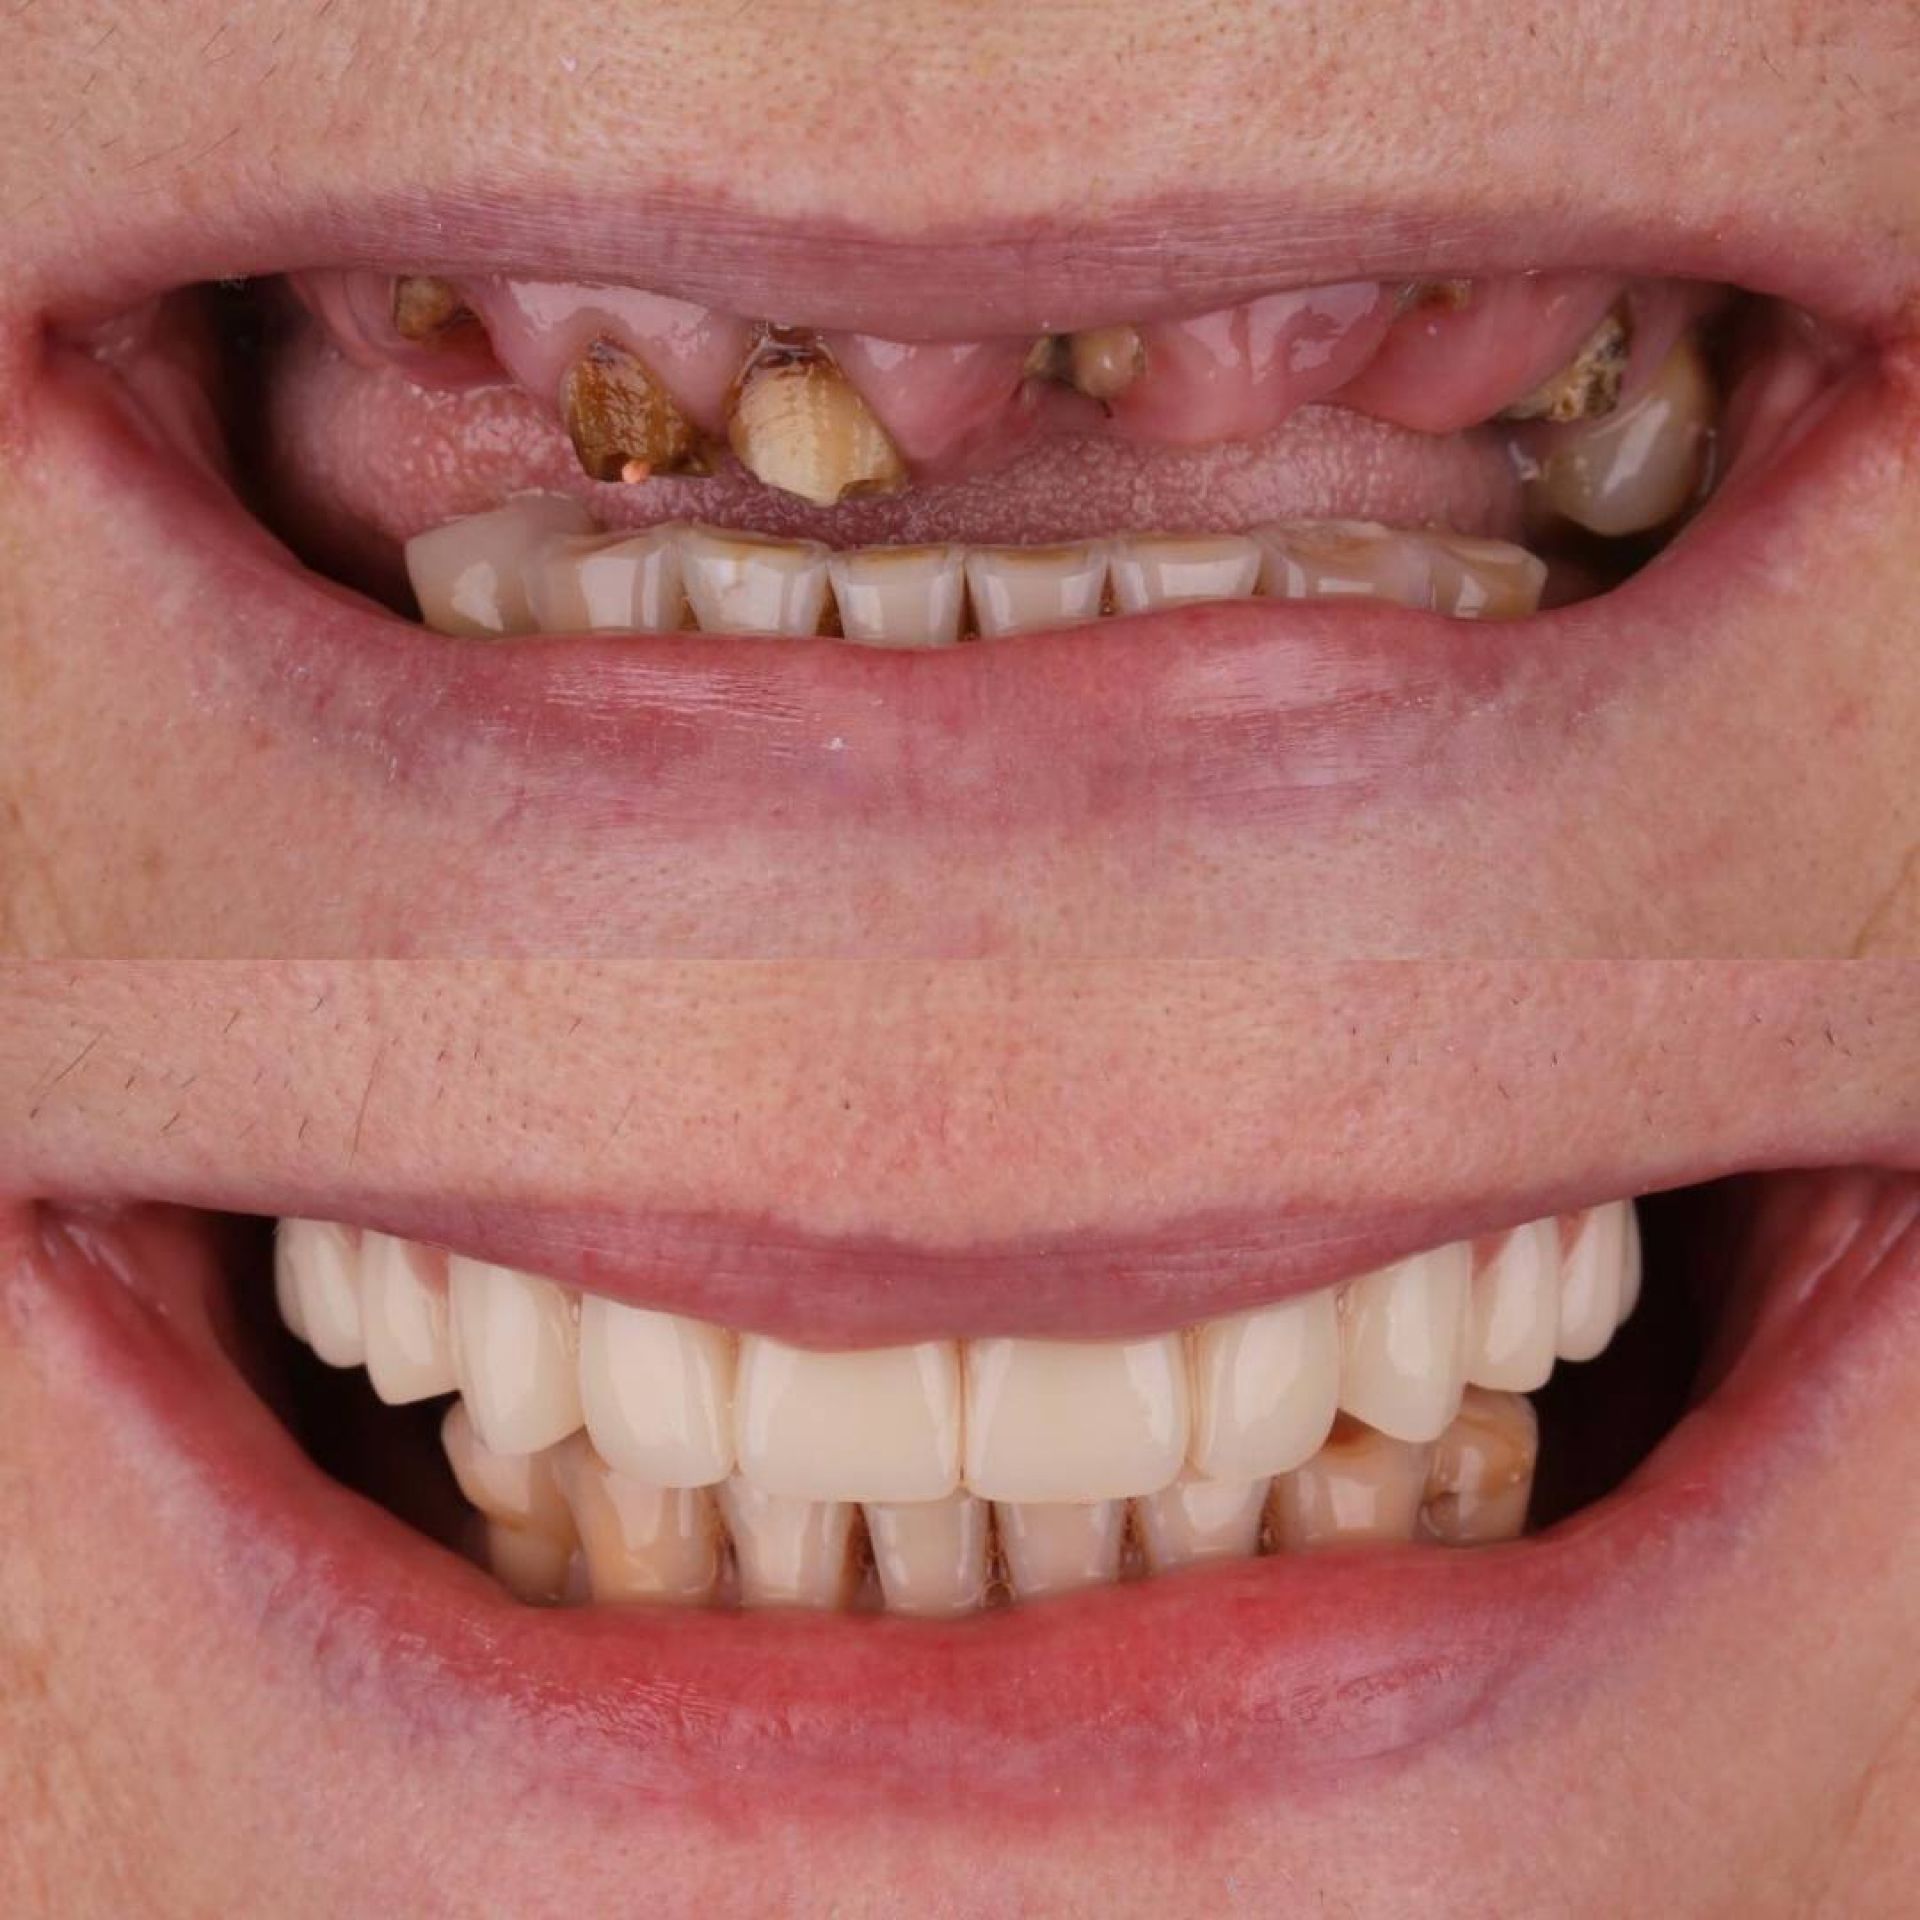

Імплантація зубів — це сучасна технологія відновлення зубного ряду, яка використовується для заміщення втрачених зубів. Цей процес полягає в установці штучного корінця зуба, відомого як імплантат, у кістку щелепи, на який потім кріпиться внутрішньоротова частина — коронка.

Завдяки імплантатам Ви назавжди забудете про дискомфорт, який спричиняє відсутній зуб або зуби. Ми якісно відновимо жування та естетику Вашої посмішки в найкоротші терміни з довготривалим результатом.

Сучасні протоколи імплантації дозволяють:

- одномоментно видаляти зуб та встановлювати імплант з подальшим протезуванням коронкою;

- відновлювати весь зубний ряд завдяки протоколам «all-on-4», «all-on-6», найкращий варіант при повній втраті зубів;